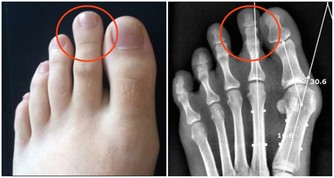

屁多尷尬,讓你費心,但是如果屁少甚至是沒有,你就更要注意,因為它更危險,無屁肚子又脹,很可能是腸道某處“封鎖”不通,多見於腸梗阻、腸扭轉,或因腸麻痺而不能驅動氣體“出境”。這就是為什麼手術後,醫生非常關心病人的放屁信息,就是祈盼“一聲響屁報平安”——這意味著腸子已通暢了。